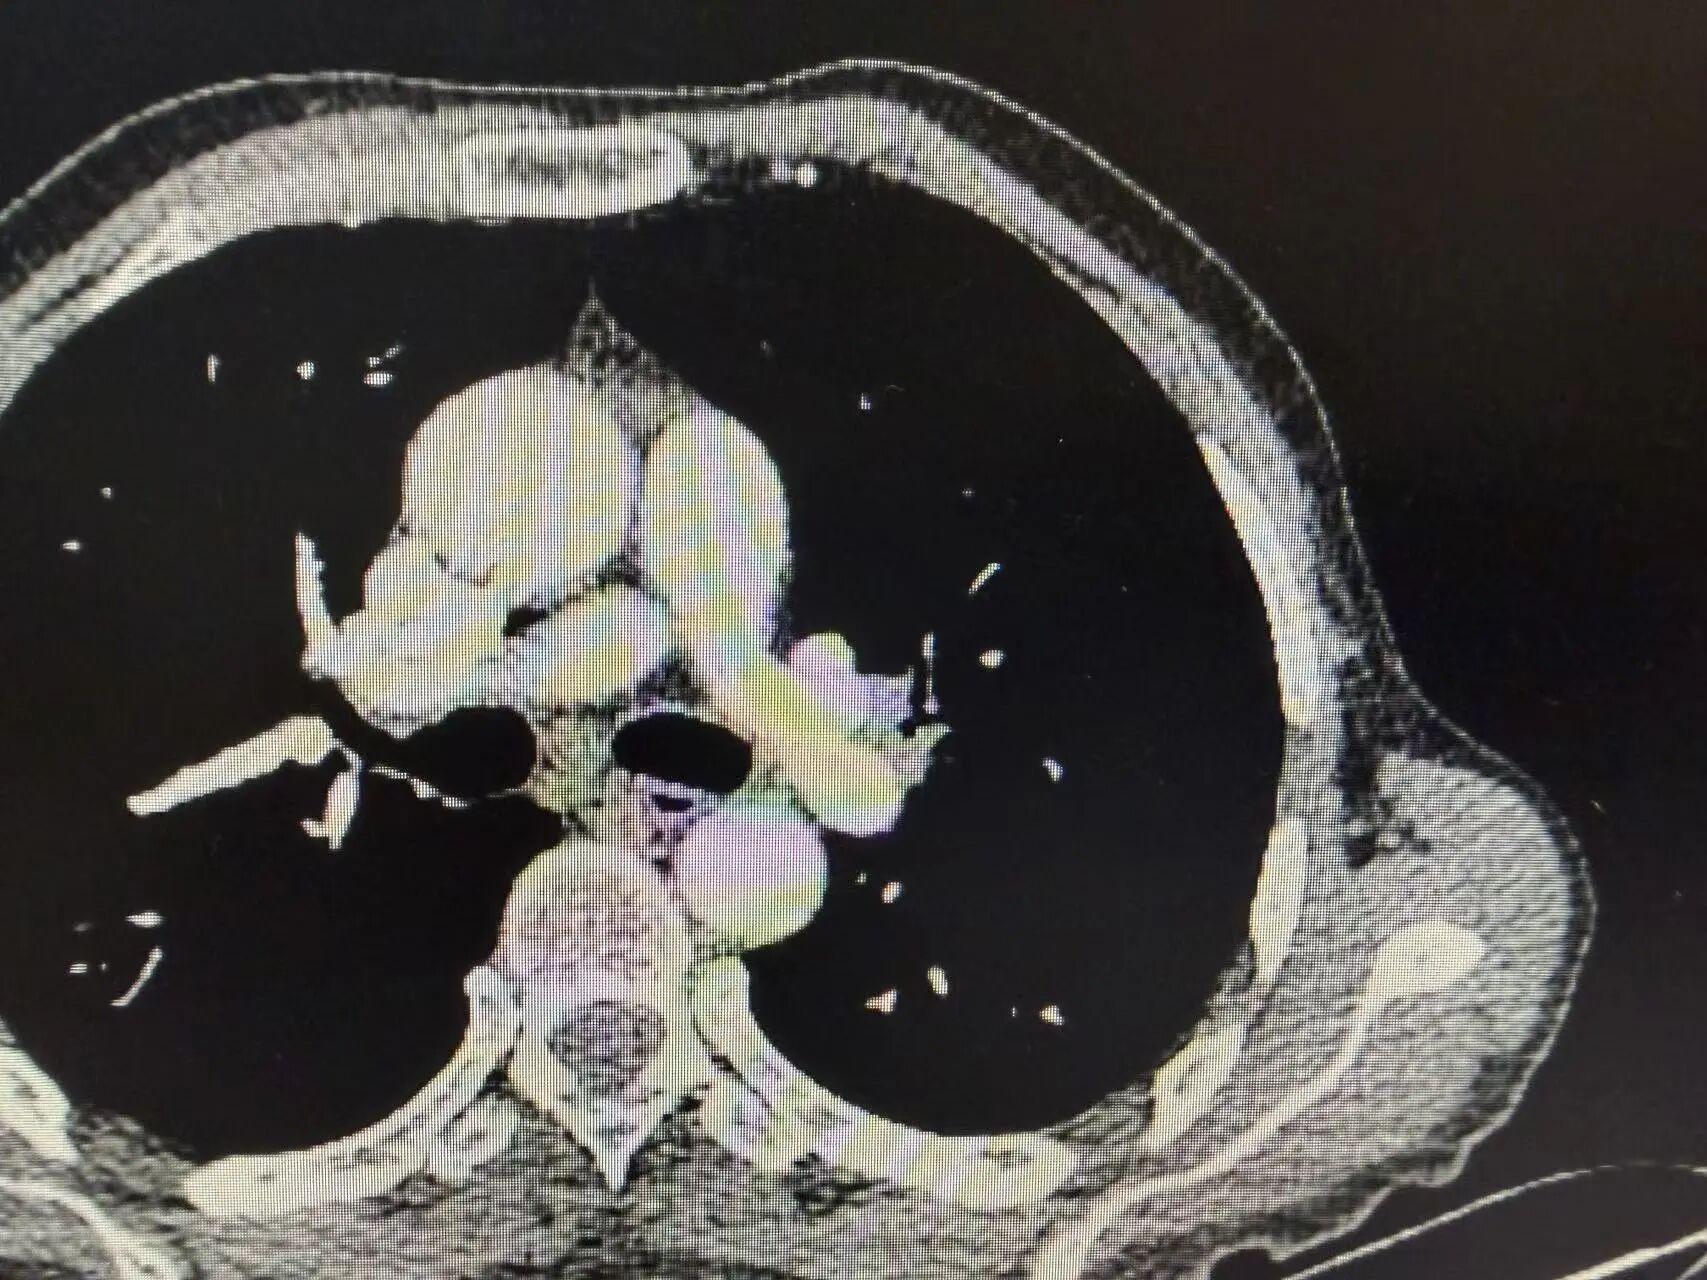

1-2.jpg

1-3.jpg

新辅助治疗前CT:可见左上肺中央型占位,肿瘤侵犯血管

1-4.jpg

1-5.jpg

新辅助治疗后CT:肿瘤明显缩小